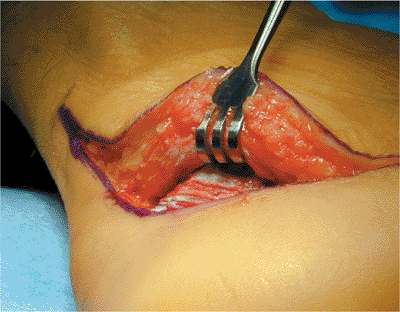

![]() |

Figure 35.11. Positioning of the patient.

predrilled and a short Schantz pin is screwed into place. Using the

(Fig. 35.19).